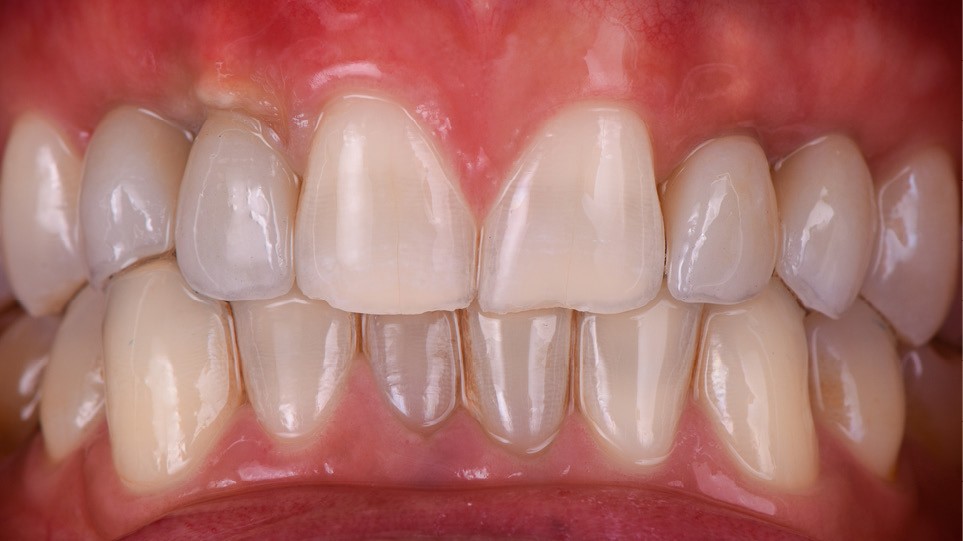

- pose des couronnes d’usage selon le protocole classique (fig. 9 et 10a) ;

Ce cas clinique met en exergue les possibilités grandissantes qu’offre le flux digital dans la prise en charge du secteur antérieur [3]. Ce dernier confère précision et prédictibilité du résultat final, tant pour le praticien (guide chirurgical) que pour le patient (modélisation via un wax-up numérique). L’alliance du numérique et de la chirurgie dans un contexte particulier d’agénésie avec une occlusion perturbée permet de répondre aux doléances fonctionnelles et esthétiques du patient avec une prothèse parfaitement intégrée aux tissus périphériques dentaires et muqueux.